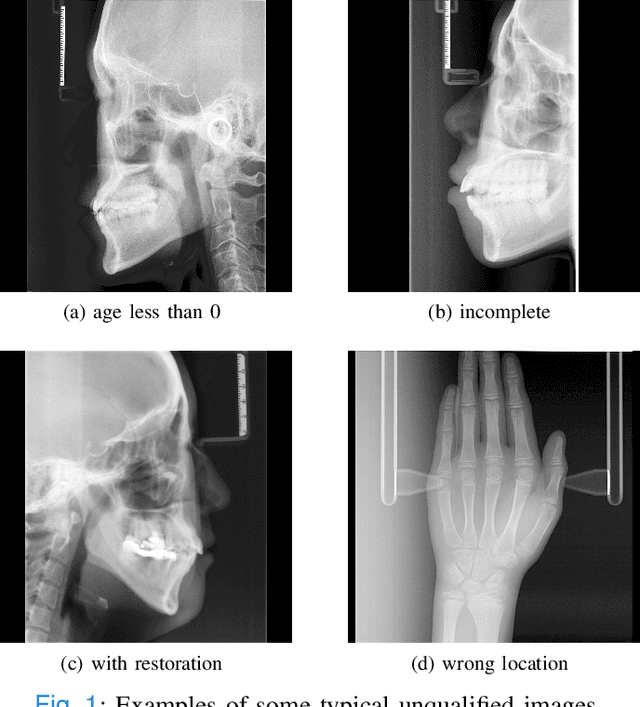

Abstract:The traditional manual age estimation method is crucial labor based on many kinds of the X-Ray image. Some current studies have shown that lateral cephalometric(LC) images can be used to estimate age. However, these methods are based on manually measuring some image features and making age estimates based on experience or scoring. Therefore, these methods are time-consuming and labor-intensive, and the effect will be affected by subjective opinions. In this work, we propose a saliency map-enhanced age estimation method, which can automatically perform age estimation based on LC images. Meanwhile, it can also show the importance of each region in the image for age estimation, which undoubtedly increases the method's Interpretability. Our method was tested on 3014 LC images from 4 to 40 years old. The MEA of the experimental result is 1.250, which is less than the result of the state-of-the-art benchmark because it performs significantly better in the age group with fewer data. Besides, our model is trained in each area with a high contribution to age estimation in LC images, so the effect of these different areas on the age estimation task was verified. Consequently, we conclude that the proposed saliency map enhancements chronological age estimation method of lateral cephalometric radiographs can work well in chronological age estimation task, especially when the amount of data is small. Besides, compared with traditional deep learning, our method is also interpretable.